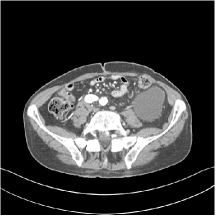

III.C.3. Analysis of Residual Maps

Here, we investigate the residual images over the layers of the MARS7 model. Fig. 12 displays the image reconstructed with MARS7 along with the residual images in different layers. The residual images are generated by applying the restoring operation to the corresponding columns of each residual matrix , forming images . Essentially, all the columns of are transformed into patches and accumulated back in the image to form the residual image in the th layer. We can observe that the residual images in the first three layers contain explicit structural information and we still find some delicate details in the fourth and fifth layers. However, we hardly see any valuable features in the residual images for the following layers, which is consistent with the fact that the transform is overwhelmed by noise in quite deep layers. Therefore, the ceiling for the potential of multi-layer sparsifying transform model may be 5 or 7 layers. The quantitive result also implies the same conclusion.